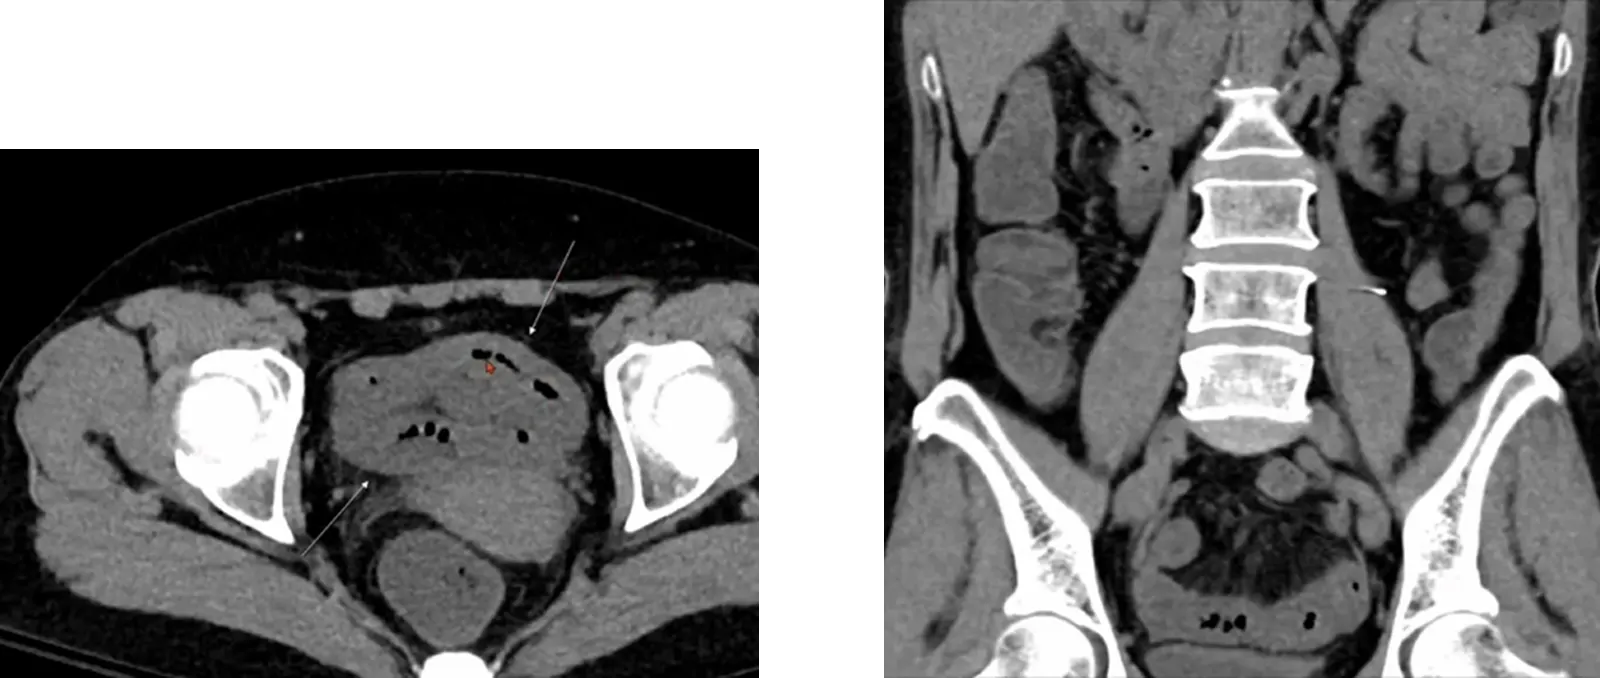

Case 10-2

•

M/43

C/C: Abdominal pain, aggravation

Hx : h/o ureter stone

Lab: within normal limit